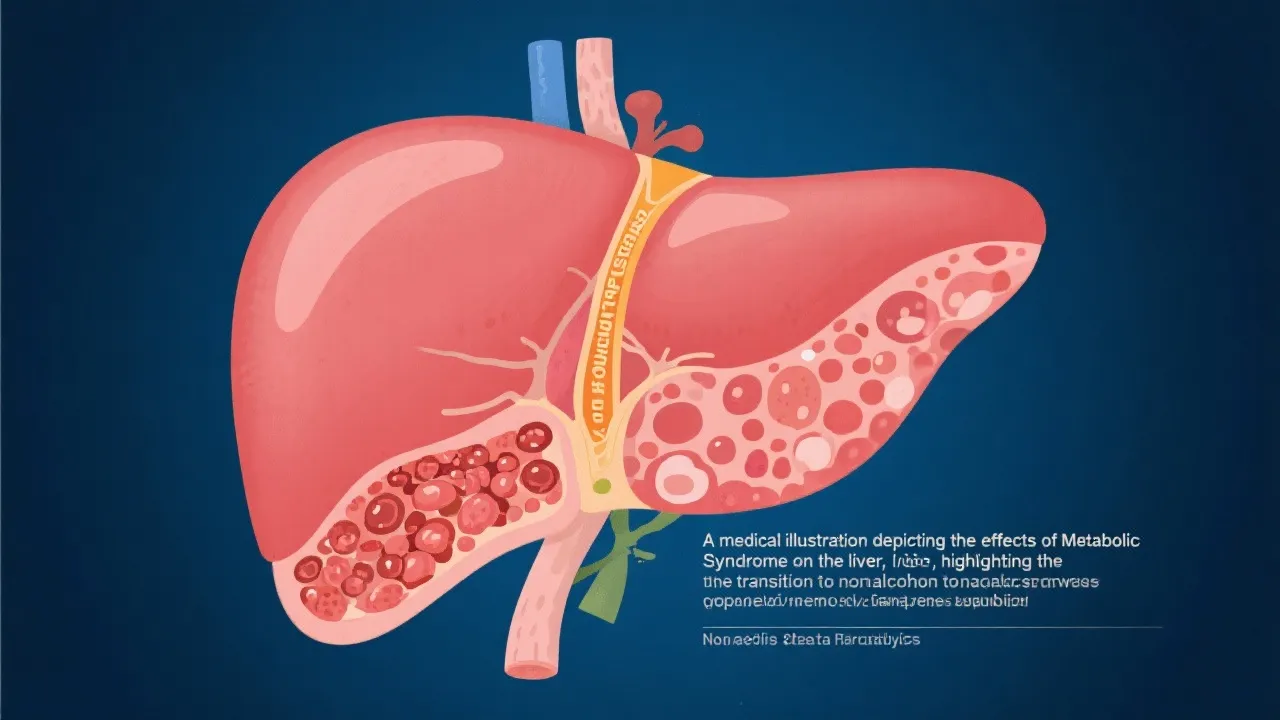

This article explores the relationship between metabolic syndrome and its influence on nonalcoholic steatohepatitis (NASH). Metabolic syndrome, a cluster of conditions including high blood pressure, high blood sugar, excess body fat around the waist, and abnormal cholesterol levels, significantly increases the risk of developing NASH, a severe liver disease that can lead to cirrhosis, liver failure, or hepatocellular carcinoma.

Metabolic syndrome is a complex condition characterized by a cluster of interrelated risk factors, significantly impacting global health. This syndrome is especially concerning, as it has a proven influence on developing nonalcoholic steatohepatitis (NASH). NASH is a severe form of nonalcoholic fatty liver disease (NAFLD), marked by liver inflammation and damage that results from fat accumulation in liver cells. As lifestyles change and obesity rates continue to rise, understanding this intricate relationship becomes crucial for public health and individual well-being.

Abdominal obesity, often measured by waist circumference, is another critical component of metabolic syndrome. It indicates visceral fat accumulation, which is considered more metabolically harmful than subcutaneous fat. The fat stored in the abdominal cavity produces inflammatory cytokines and hormones that contribute to various metabolic complications. Individuals with abdominal obesity face increased stress on liver detoxifying responsibilities and are prone to hepatic steatosis, or the buildup of fat in liver cells. This condition is not benign; instead, it paves the way for further inflammation and scarring, culminating in NASH. Therefore, addressing abdominal obesity is essential in managing not only metabolic syndrome but also preventing the progression to more severe liver diseases.

To grasp the connection between these two conditions, it is crucial to understand how the components of metabolic syndrome alter liver function and health. Excessive free fatty acids in the liver due to lipid overflow compromise liver function, instigating steatosis. When combined with insulin resistance, these stress substrates further the inflammatory response, inducing hepatocyte injury and fibrogenesis—hallmarks of NASH. This intricate interplay describes a vicious cycle: as liver fat accumulates, it incites an inflammatory response that promotes further fat infiltration and liver damage.

An important aspect of this pathophysiological process is the concept of "two-hit hypothesis." The first hit refers to the accumulation of fat in the liver, which, while initially reversible, creates a susceptible environment for injury. The second hit involves the inflammatory and fibrotic response to this fat accumulation, leading to oxidative stress and hepatocyte apoptosis (programmed cell death). This duality suggests that both lifestyle modifications aimed at reducing fat and targeted interventions toward alleviating inflammation are integral in halting and potentially reversing the progression from simple steatosis to NASH.